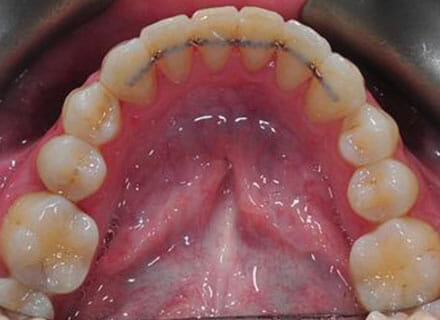

In this case the whole smile was affected by a tooth that was missing (a visible gap or hole at the side when smiling) and a tooth at the front that had grown the wrong side of the bite. We were able to correct the gap at the back by pulling the tooth behind forwards into the gap left by the previous extracted tooth. The clear brace also pushed the tooth at the front back in to the right position and the smile was massively improve. This case took around 18 months to complete.